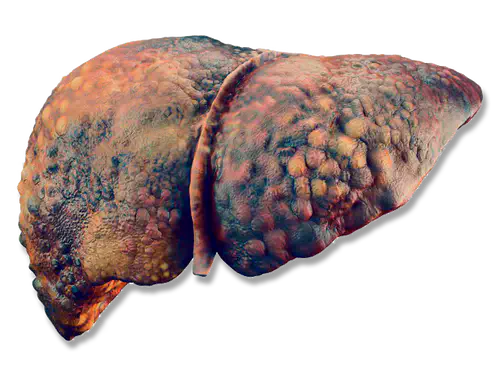

QUAIS SÃO AS CONSEQUÊNCIAS DA INFLAMAÇÃO

Se nada for feito, um fígado gordo pode levar à cirrose hepática, condição grave que requer grandes mudanças no estilo de vida.